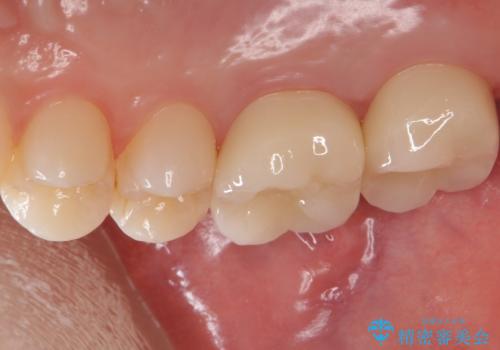

- 右上67 仮歯+ジルコニアクラウン:11,000円×2+121,000円×2 費用は治療当時の料金となります

奥歯で咬合力の負担を考慮した結果、インレーやアンレーではなくクラウンをおすすめする場合があります。